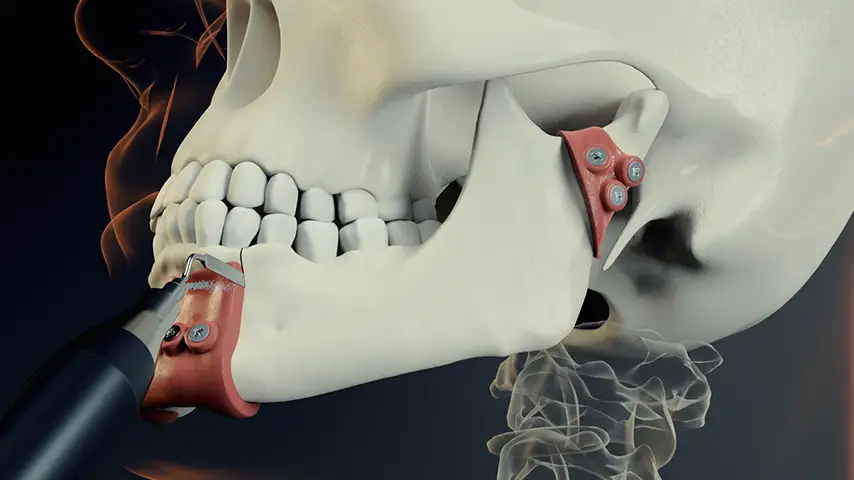

Mandibulotomy and mandibulectomy / maxillectomy

Osteotomies for harvesting and remodelling

Advantages over traditional tools

Reduced risk of damaging anatomically complex regions

Greater intraoperative control and bone management

Micrometric cut for minimal bone loss

Reduced heat generation to avoid bone necrosis